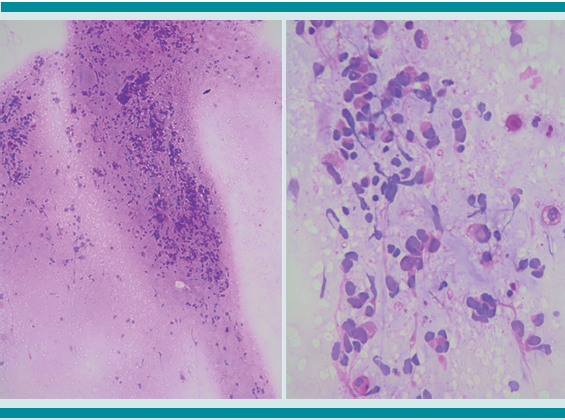

En el primero se recibió la biopsia del tumor, referido como cérvico-torácico, donde se observó una neoplasia de aspecto fusocelular, compuesta por células con atipia moderada y citoplasma amplio (Figura 5); sin embargo, el tejido fue insuficiente para inmuno-marcaje y determinación de la estirpe histológica, por lo que se estableció el diagnóstico de neoplasia maligna de origen a determinar.

En el segundo estudio se recibió mayor cantidad de tejido; esta vez se estableció el diagnóstico de “compatible con tumor rabdoide extrarrenal”, añadiendo el comentario que el tejido era muy pequeño y podía corresponder a una neoplasia heterogénea, por lo que se sugirió la correlación con los hallazgos clínicos, estudios de imagen y, de ser posible, obtener una nueva biopsia.

Además, se obtuvo una biopsia de médula ósea (que también fue insuficiente para establecer el diagnóstico) y resección del tumor torácico, que coincidió con una neoplasia con áreas extensas de necrosis, con células semejantes a las anteriormente descritas. Figura 6

El estudio de inmunohistoquímica reportó positividad para vimentina, CK-7, focalmente positivas para miogenina y negativas para INI-1. Figura 7

El tumor rabdoide extrarrenal contiene células de aspecto rabdoide, que pueden aparecer en otro tipo de neoplasias como: sarcoma sino vial, condrosarcoma mixoide extraesquelético, leiomiosarcoma, sarcoma epitelioide y en el componente mesenquimatoso de los teratomas.